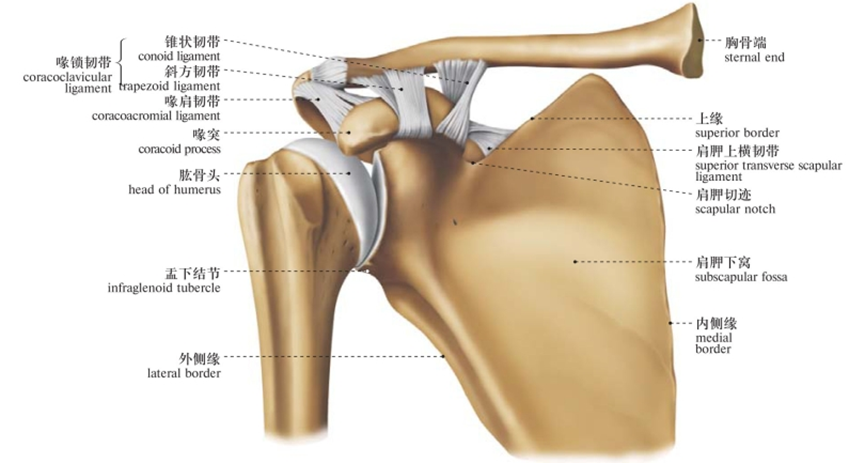

由肩胛骨的关节盂与股骨头组成,又叫肩肱关节(盂肱关节)。是典型的多轴球窝关节,为全身最灵活的关节,可作三轴运动,即冠状轴上的屈和伸,矢状轴上的收和展,垂直轴上的旋内、旋外及环转运动。

因肱骨头较大,呈球形,关节盂浅而小,仅包绕肱骨头的1/3,关节囊薄而松弛,所以是人体运动范围最大而又最灵活的关节。

肩关节的连结

肩锁关节(AC):锁骨远端与肩胛骨肩峰突的交汇点。

胸锁关节(SC):锁骨近段与胸骨 、第一肋的交汇点。这是一个相对较小的关节,它起到了连结肩臂与中轴骨(胸廓)的作用。

盂肱关节(GH):肱骨的球面端嵌入肩胛骨关节窝所形成的凹面;大部分人会认为盂肱关节就是“肩关节”。

肩胛骨-胸廓关节(ST):严格来说它并不是一个关节(关节的定义是两块骨骼的交汇点),而是肩胛骨与胸廓后外侧的接触位置。一块肩胛骨通过17块肌肉的协同作用,与肱骨共同完成动作(灵活性),同时也为理想的体资及过顶动作创造足够的支撑(稳定性)